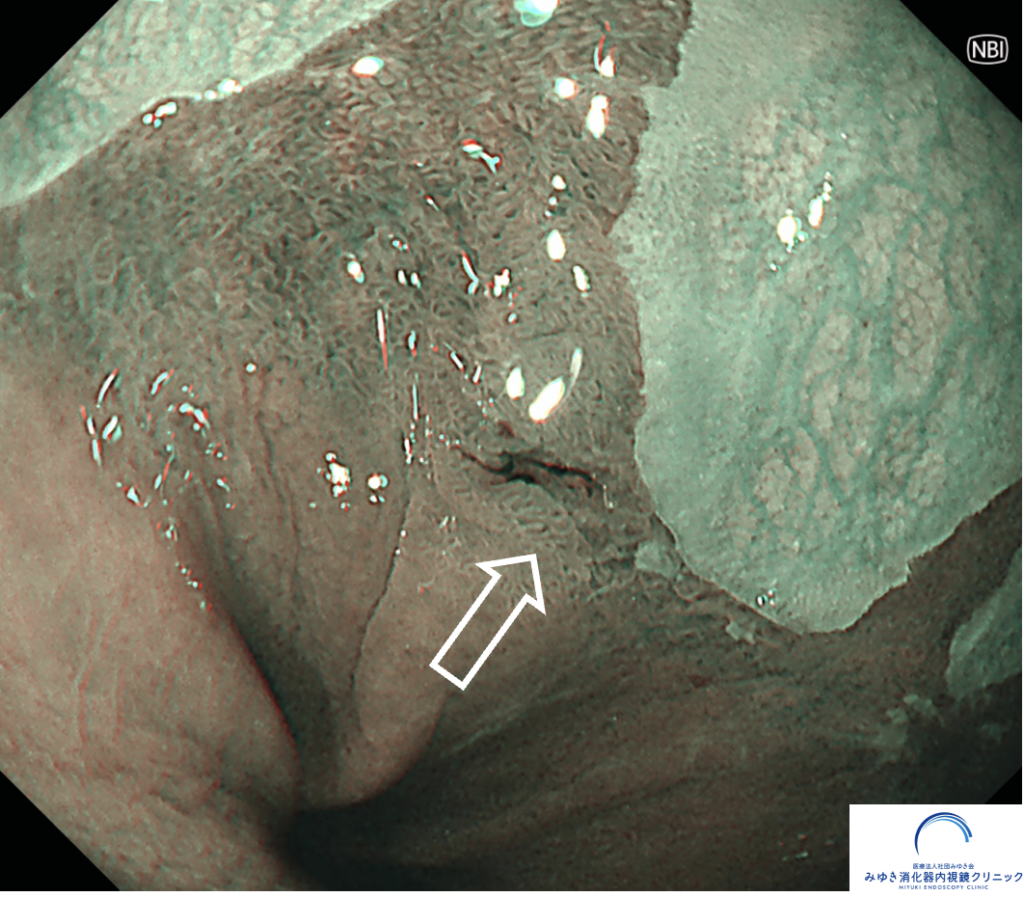

NBI観察

<特殊光(NBI・TXI)での精密観察が重要>

そのため診断には、通常光に加えて、

NBI(狭帯域光観察)

TXI(構造・色調強調観察)

といった 画像強調内視鏡(IEE) を組み合わせて、粘膜の微細な血管・表面構造を詳細に観察します。

こうした特殊光観察は、数mmレベルの早期バレット食道がんの発見に非常に有用 です。

ただし、バレット食道がんは胃がんと比べて、がんの広がり(境界)が分かりにくいという特徴があります。

炎症が重なっていたり、色調の差が微妙だったりするため、

・NBI

・TXI

・拡大観察

など、特殊な観察方法を駆使して病変を慎重に見極める必要があります。